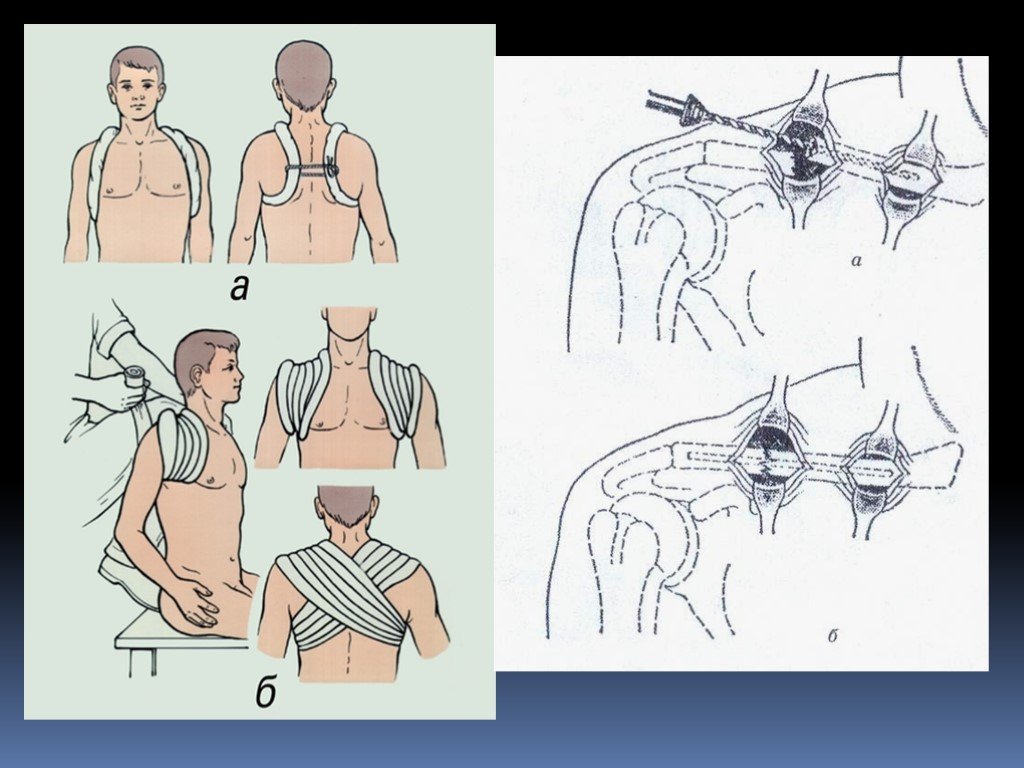

Вывихи и переломы ключицы презентация - 85 фото